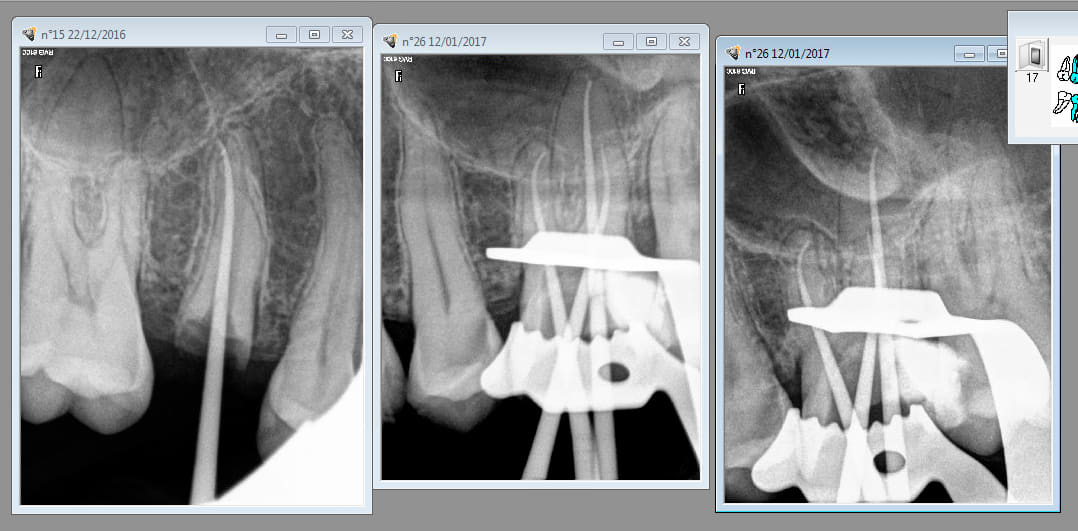

pis tiens un contre exemple , je ne suis pas chicot , j'ai pas tout ton matériel , je ne condense rien , ni à chaud ,ni à froid et pourtant ça sort pas mal !!! Comme quoi faut pas se fier aux photos , on peut tout faire avec ....

T'as quel capteur radio et avec quel logiciel? as-tu modifié des parametres? tu utilises quel ciment?

RVG trophy , ciment : Acroseal de SEPTODONT ,je crois que Chicot a une trophy aussi ...

Ah oui le logiciel y fait beaucoup parce que avec un même capteur et une mise à jour logiciel j'ai vraiment vu la différence de netteté !